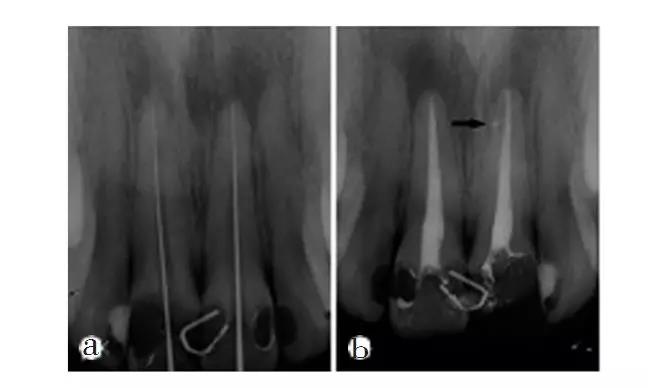

由于牙周炎症引起的牙髓组织感染称为逆行性牙髓炎。逆行性牙髓炎是常见病。牙周组织的破坏如牙周膜、牙槽骨严重吸收时的炎症,可以引起牙根尖的感染,通过根管引起牙髓组织发炎。逆行性牙髓炎产生的症状与一般牙髓炎的症状基本相同,如遇到冷、热水疼痛,白天和夜间的自发痛等。不同的是,一般牙髓炎是由于牙齿龋坏而引起的,牙齿上有龋洞,逆行性牙髓炎的牙齿没有龋坏,主要是牙齿周围的组织发炎而引起,可以发现牙周组织内有脓,牙龈可以发炎红肿。逆行性牙髓炎有明确的牙周炎病史,牙X线片检查发现牙周组织严重破坏,牙槽骨严重吸收。

正确的牙髓活力判断决定了临床治疗计划的合理性。目前临床上测试牙髓活力的方法有感觉测试和血流测试,并且主要是电测试、温度测试等感觉测试。血流测试由于技术和成本问题目前并未广泛应用于临床,没有一种牙髓活力测试方法临床上能够准确判定患牙牙髓活力状态。有研究表明,联合运用冷测和电测可提高测试结果的准确性。为了临床上更好的判断牙髓活力状态,并获得准确的判断结果,特提出牙髓活力状态判断的临床路径和操作规范,供大家参考。

⑦对牙髓活力进行判断进而进行临床诊断时,应以测试结果为依据结合患者临床症状体征以及影像学检查综合进行判断。应尽可能分析易导致假阳性或假阴性结果的因素,谨慎做出判断。